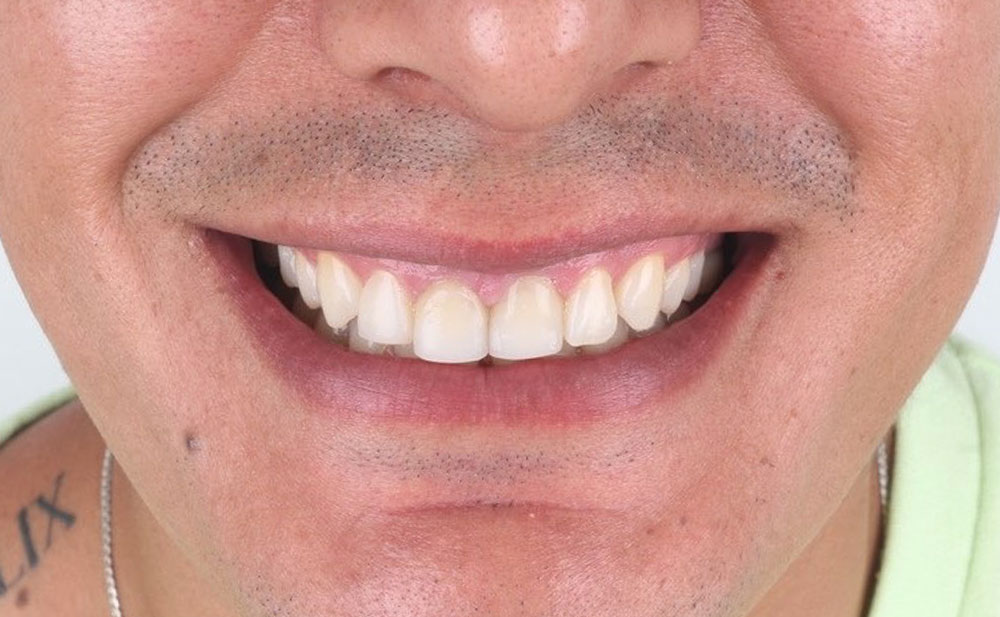

Después

Después

Después

Después